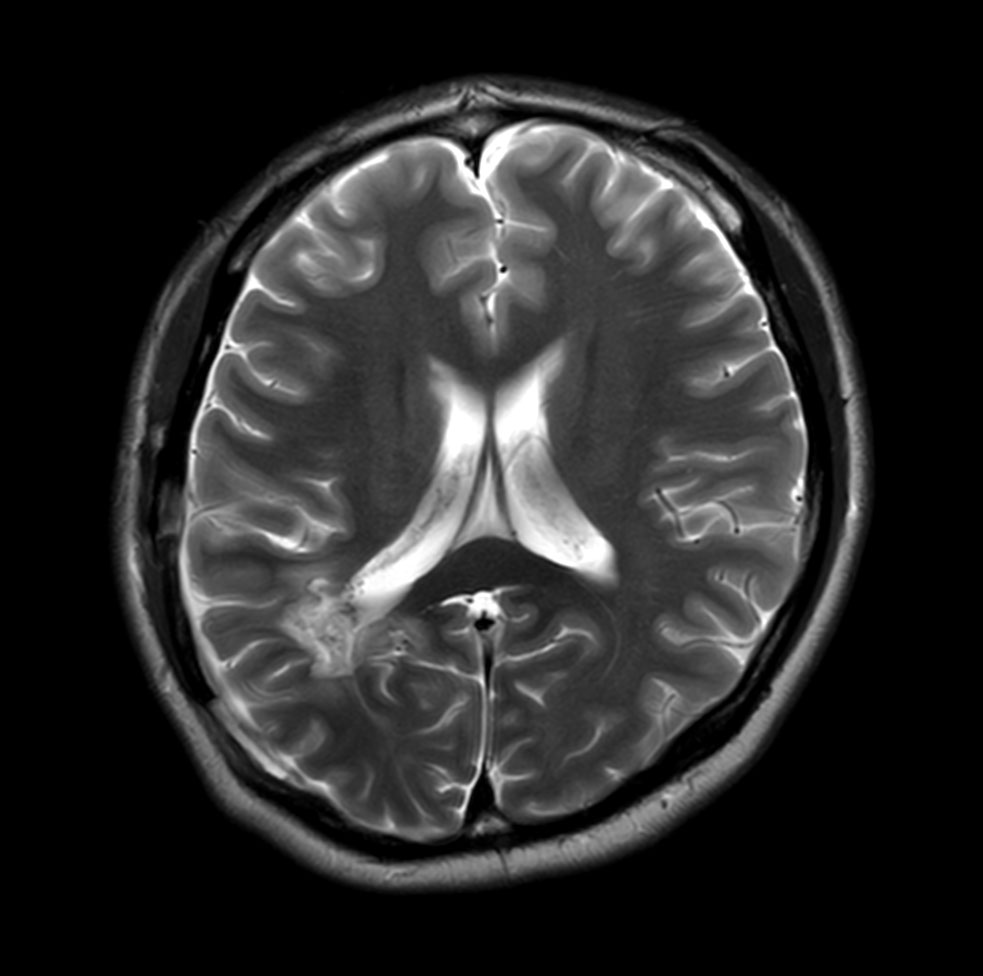

Axial T2w TSE